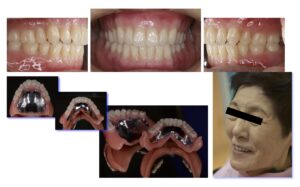

治療後 最初に治療用義歯を装着することにより、傷ついた土台の粘膜の改善と噛み合わせの正常化を図られたことから、最終義歯としてBPS義歯を装着しました。義歯の吸着は良好で、患者さんの生活の質(QOL)は向上し、大変満足いただけました。

3. 最終義歯(カラーリングBPS義歯)の製作と装着

治療用義歯の装着により「よく噛めるようになった」とのお話が聞け、入れ歯の土台となるあごの粘膜が健康になって、下顎左側偏位の修正が得られました。そこで最終義歯(BPS金属床義歯)を製作していくこととしました.製作ステップは治療用義歯製作と変わりません。見た目を綺麗にしたいとのご要望があり、歯肉の相当する部分をカラーリングして、より自然感のある美しい義歯に仕上げました。患者さんの笑顔も見られ、初診時に障害されていた生活の質(QOL)も70満点中14点と全ての項目で向上して、ご満足が得られました。

【治療概要】治療用義歯を装着して機能改善を図った上で,最終の上下顎総入れ歯を装着した

【入れ歯の種類】上下顎治療用義歯,上下顎カラーリングBPS総義歯

【メインテナンス開始までの治療期間】6ヶ月

【メインテナンス開始までの治療回数】12回

【リスクと副作用 】下顎前方偏位(前噛み癖)があることから、上顎前歯部残存顎堤への負担が大きい

【費用】上下顎治療用義歯 : 44×2 万円,上下顎カラーリングBPS金属床義歯:88×2 万円